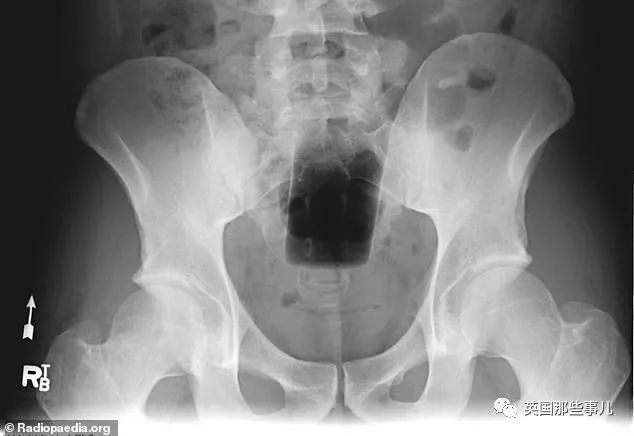

“噴霧罐子”

“莫名其妙的壹個瓶子”